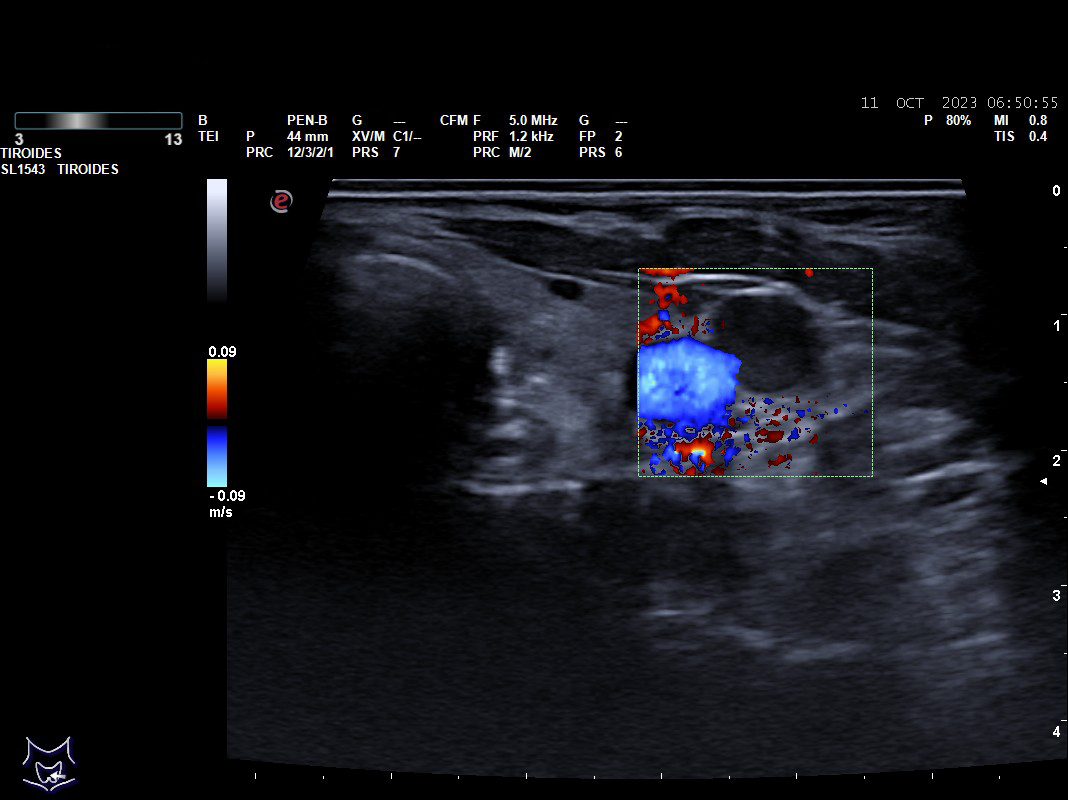

Hallazgos ecográficos: nódulos tiroideos subcentimétricos sin cambios, yugular interna izda con contenido discretamente hiperecogénico que no capta Doppler y colapsabilidad incompleta.

Se deriva a urgencias es valorada por cirugía vascular quienes describen la presencia del trombo sin poder precisar su final y se ingresa a la paciente ya que el servicio de radiología no considera realizar en ese momento el estudio pertinente.

Tras cinco días de ingreso se realiza un ecodoppler reglado descartándose la trombosis venosa, se suspende la anticoagulación y se da de alta sin tratamiento.